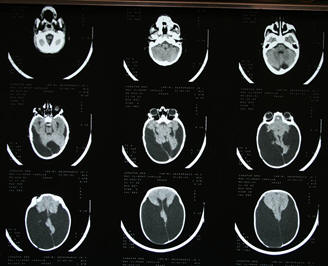

Camille Maryse McClymont, 22, who was born in Paisley, suffered from severe microcephaly. Her CT scans are reproduced below. She died in 2013 but her spirit inspired the development of a facility for adults with disablities in France and a care home in Cornwall - both of which have been named after her in tribute.

The Royal Alexandra Hospital in Paisley strongly denied there was anything out of the ordinary during the birth. Incongruously, this same hospital, at the time they were denying this, also informed L’Hôpital des Enfants in Bordeaux that during the birth, Camille suffered from hypoxia. I include a copy of a brain scan taken just before the shunt was put in. So, this answers the question by the French doctors of what exactly did the Scottish doctors know? Well, everything! However, as our original GP in Paisley put it, “No doctor will shop another doctor.”